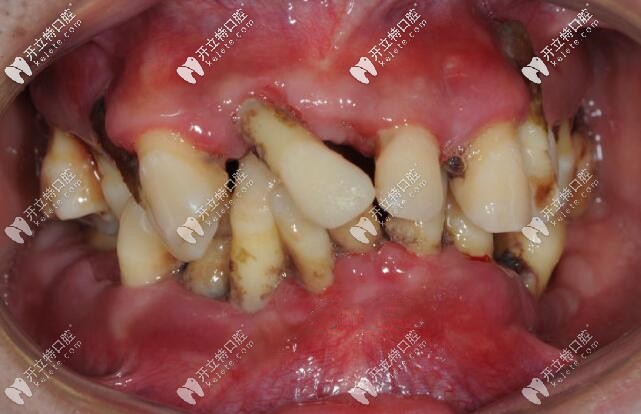

案例二、35歲大叔,全口牙槽骨重度吸收,全部牙齒都漂浮在骨頭之上,后來(lái)也是拔掉了全部牙齒,做了活動(dòng)義齒。

35歲重度牙周炎顧客的牙齒情況